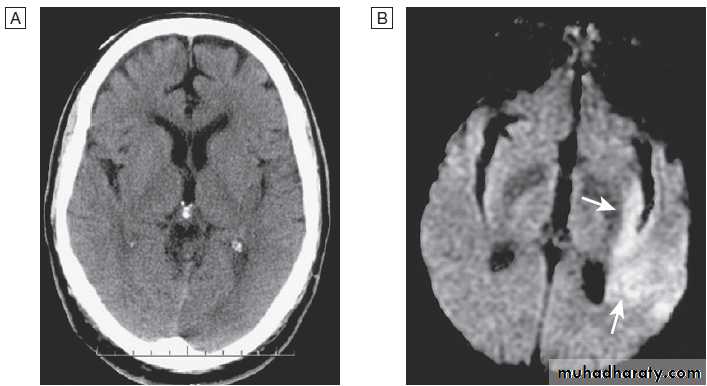

Acute stroke seen on CT scan with corresponding MRI appearance.

A CT may show no evidence of early infarction.B Corresponding image seen on MRI diffusion weighted imaging (DWI) with changes of infarction in middle cerebral artery (MCA) territory (arrows).